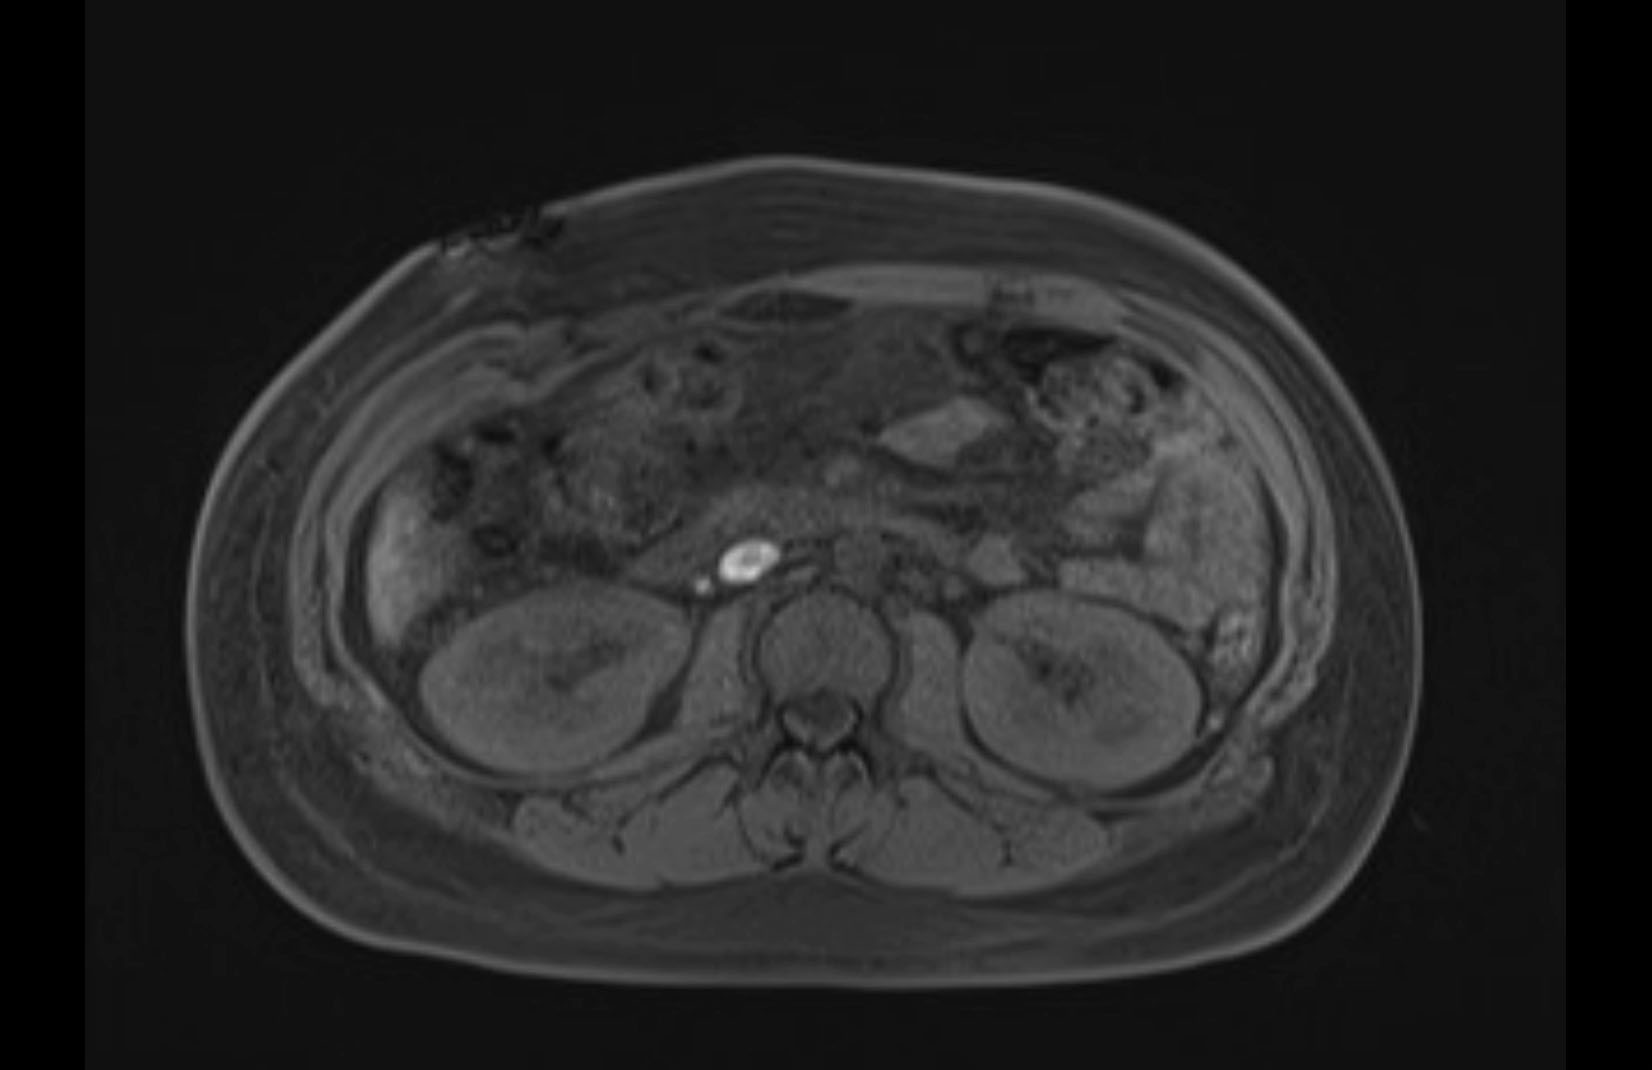

Imaging Analysis

Look through the patient's CT scan to identify any areas of concern for the necessary procedure.

MRI T1

MRI T2

Based on initial findings, which issue(s) would you be most concerned about?